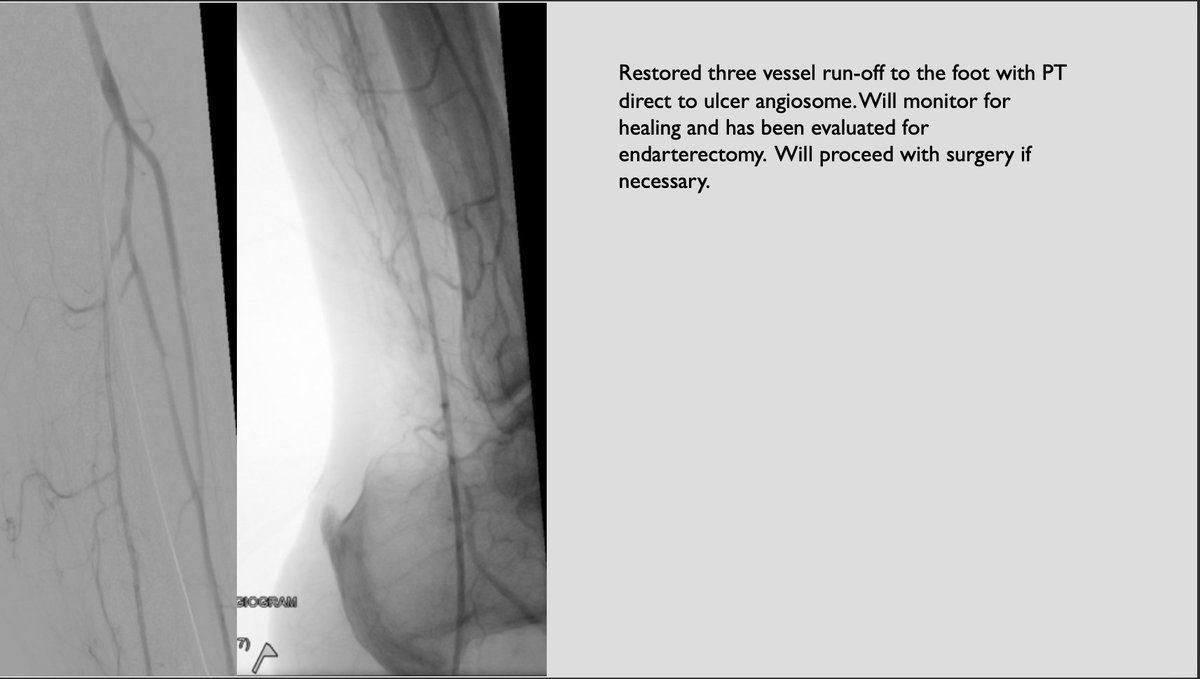

First 🇺🇸 case with Philips Healthcare 1.5 Phoenix atherectomy. Ca++ occluded CFAs preclude access. Iliac occlusion treated transradial. 4Fr access to PT with 1.5 Phoenix making short work of tibial calcium. Restored three vessels to the wound. #irad #CLIfighters #HumbledandHonored

First 🇺🇸 case with <a href="/PhilipsHealth/">Philips Healthcare</a> 1.5 Phoenix atherectomy.  Ca++ occluded CFAs preclude access.  Iliac occlusion treated transradial. 4Fr access to PT with 1.5 Phoenix making short work of tibial calcium.  Restored three vessels to the wound. #irad #CLIfighters #HumbledandHonored